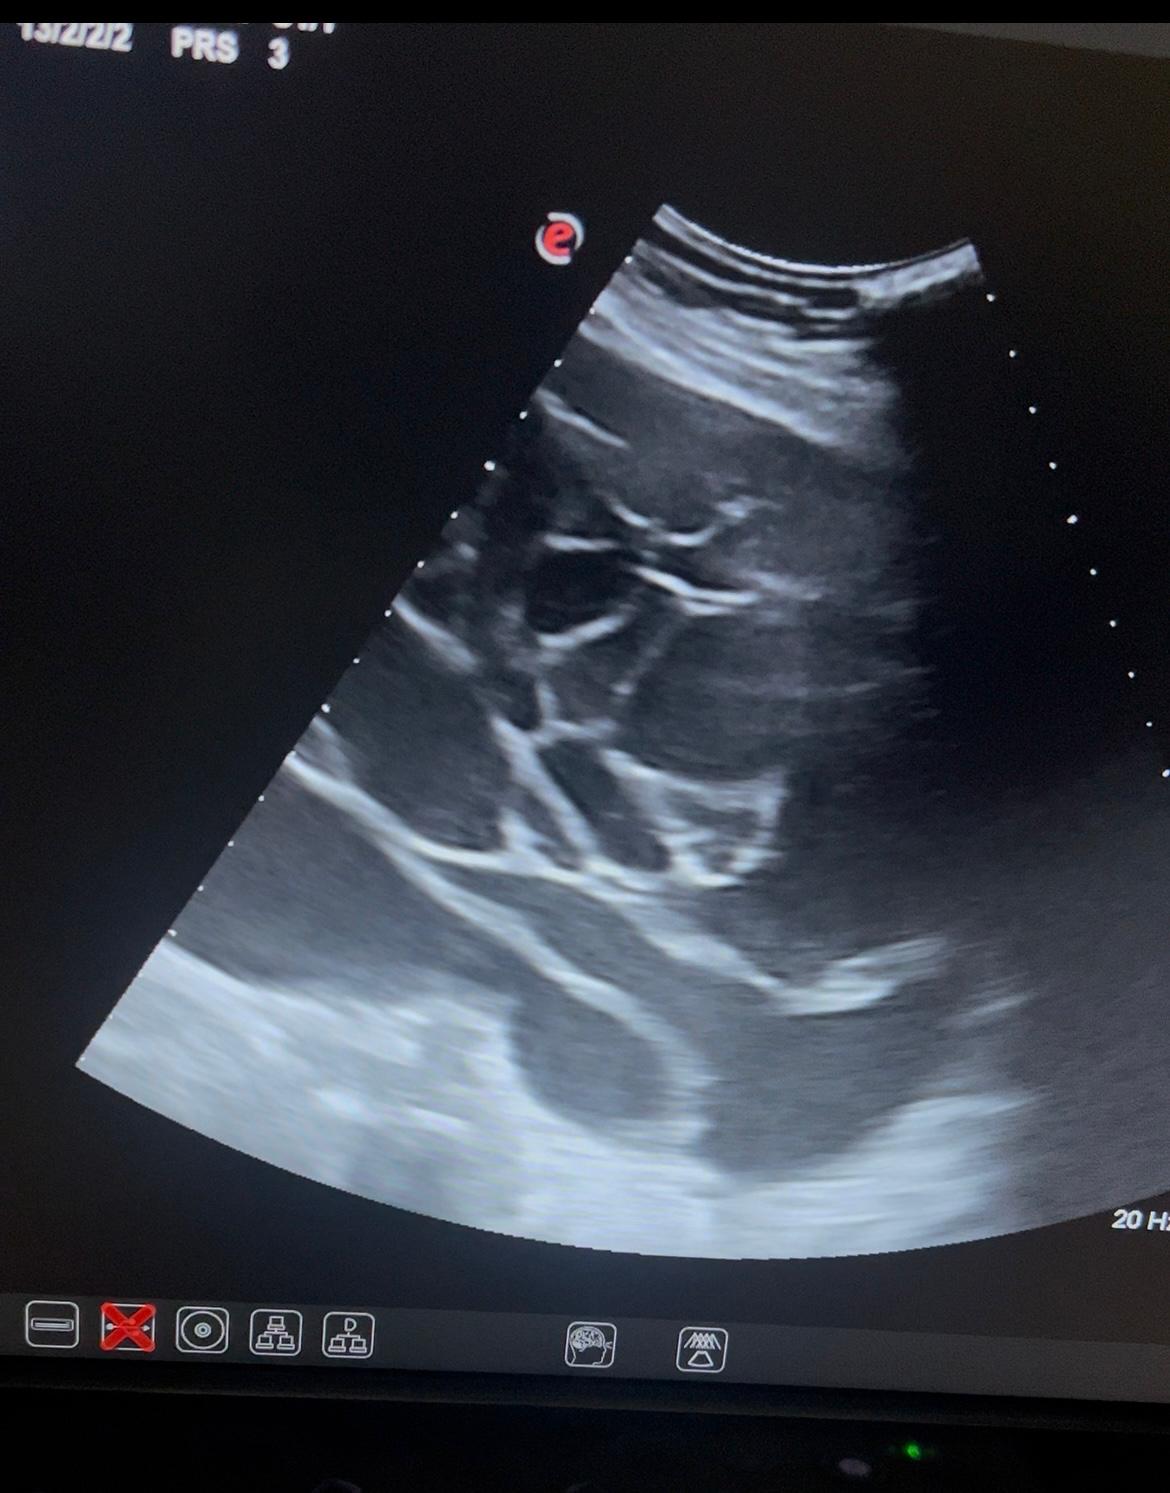

Ante la clínica discordante con la exploración procedemos a la ecografía abdominal en consulta.

Hallazgos ecográficos

Juicio clínico: tumoración ovárica izquierda a filiar. Sospecha cistoadenoma mucinoso.

Evolución: en urgencias hospitalarias Eco-TV visualizando imagen quística, multiloculada, sin captación de doppler, sin papilas sólidas en su interior, con punteado fino, de 23x12 cm. Solicitan analítica con marcadores tumorales y cita preferente en consulta de masas anexiales.

En consulta de masas anexiales Eco TV: ovario izquierdo aumentado de tamaño a expensas de una lesión multilocular de 24 x 18 cm, con lóculo de mayor tamaño de unos 14 cm. La lesión no presenta tabicaciones gruesas ni lesiones papilares sospechosas, un patrón ecográfico de cistoadenoma mucinoso ovárico GIRADS 3.